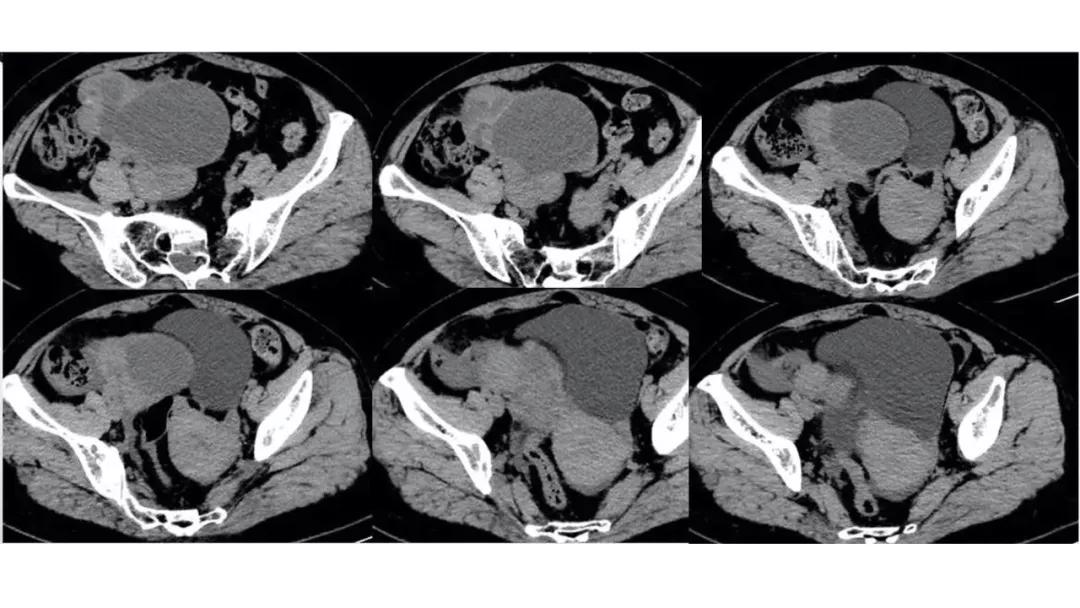

病例4 女,32岁,以“月经量增多伴经期延长半年。”

缘于患者入院前半年无明显诱因出现月经量增多,卫生巾由原来3包余增至5包不等,伴血块,经期由原来7天延长至10-15天不等,无痛经,无月经周期改变,无阴道异常排液,无畏冷、发热,无头晕、乏力等不适,未重视,未诊治。期间症状持续。2月前就诊我院,查彩超示:“子宫体大小约5.7*5.3*4.6cm,内膜厚约0.6cm,回声不均,左卵巢旁探及大小约4.2*3.5cm低回声区。”建议治疗,患者及家属表示考虑。期间症状持续,今就诊我科门诊,要求住院手术治疗,无腹痛等不适,门诊拟“卵巢囊肿”收住入院。既往史:2007年剖宫产一次,术顺。月经史:15 7/25 lmp2018.05.14,量中,无痛经。婚育史:已婚,1-0-3-1,末孕2007年剖宫产娩一男婴,儿子及丈夫体健。个人史、家族史均无特殊。

CA125 335.5(U/mL);2018-05-30 彩超:子宫宫体大小约5.6㎝×6.3㎝×4.9㎝,形态正常,宫壁回声欠均,内膜厚约1.8cm,回声不均。CDFI:子宫内未见明显异常彩色血流信号。左附件区探及一混合回声团块,大小约9.8㎝×7.9㎝,CDFI:其实性部分可见少许彩色血流信号。右附件区未见明显包块回声。

病理:卵巢子宫内膜样癌